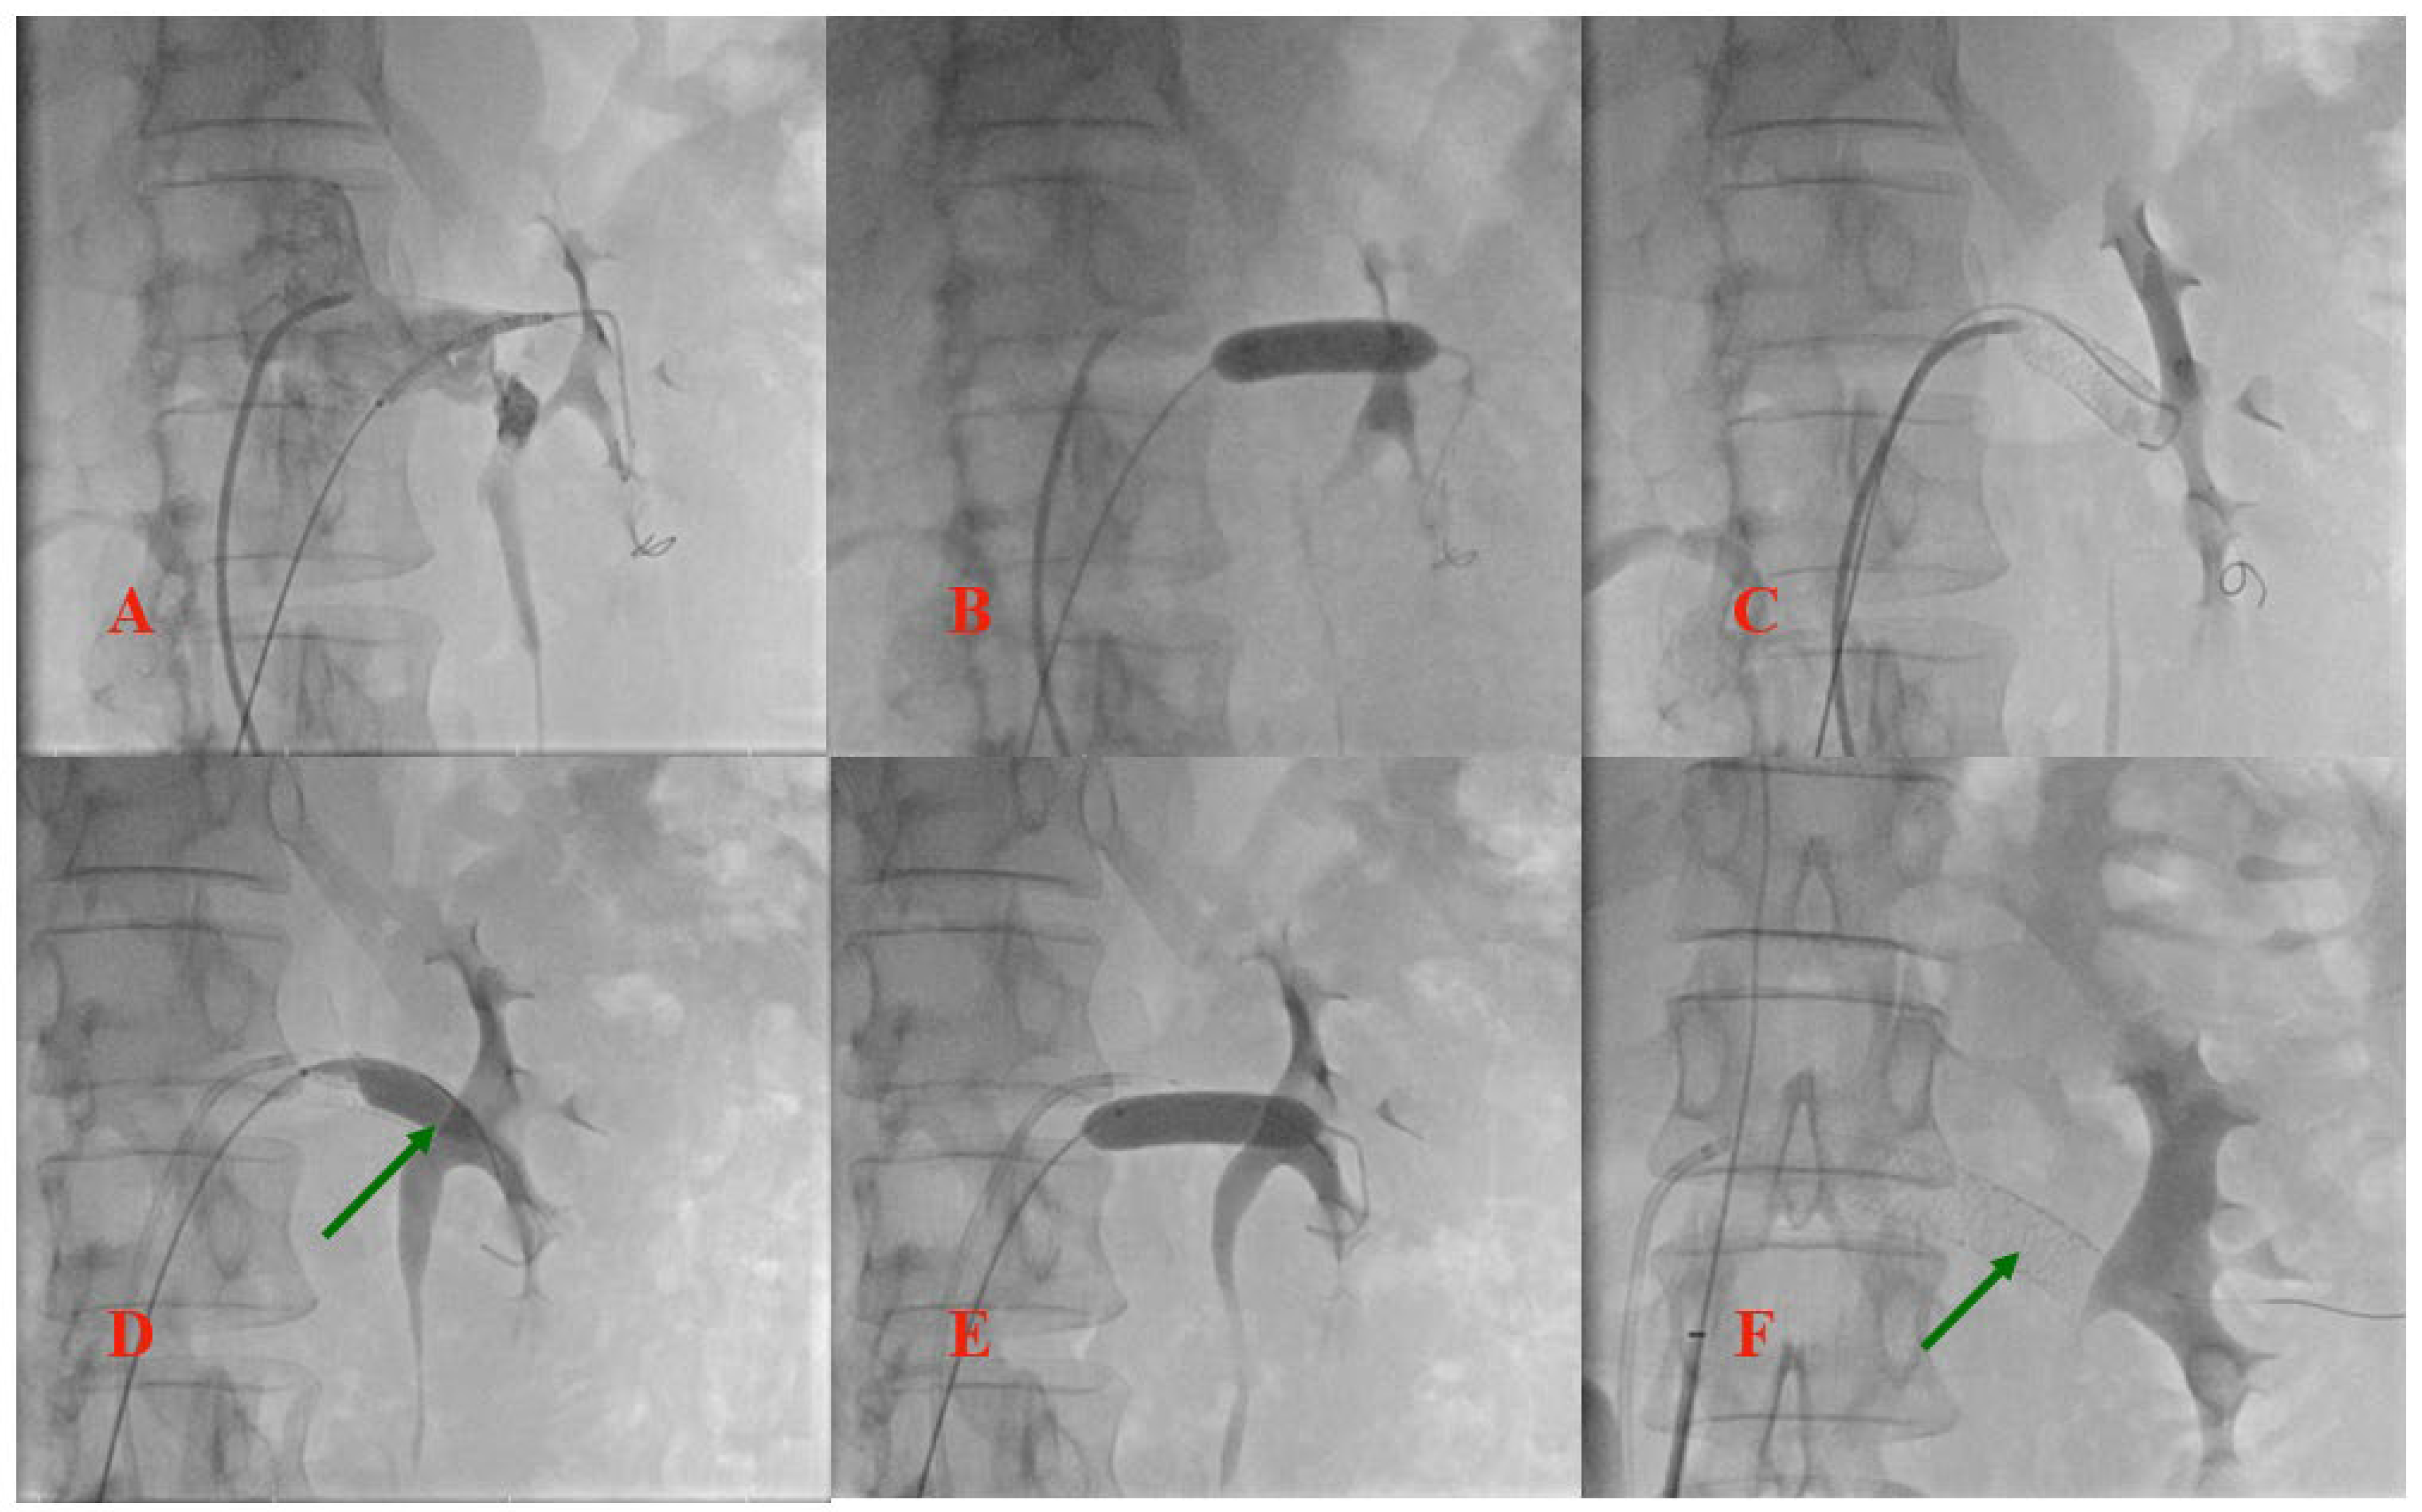

3.1. Case Report

3.2. Stent Migration